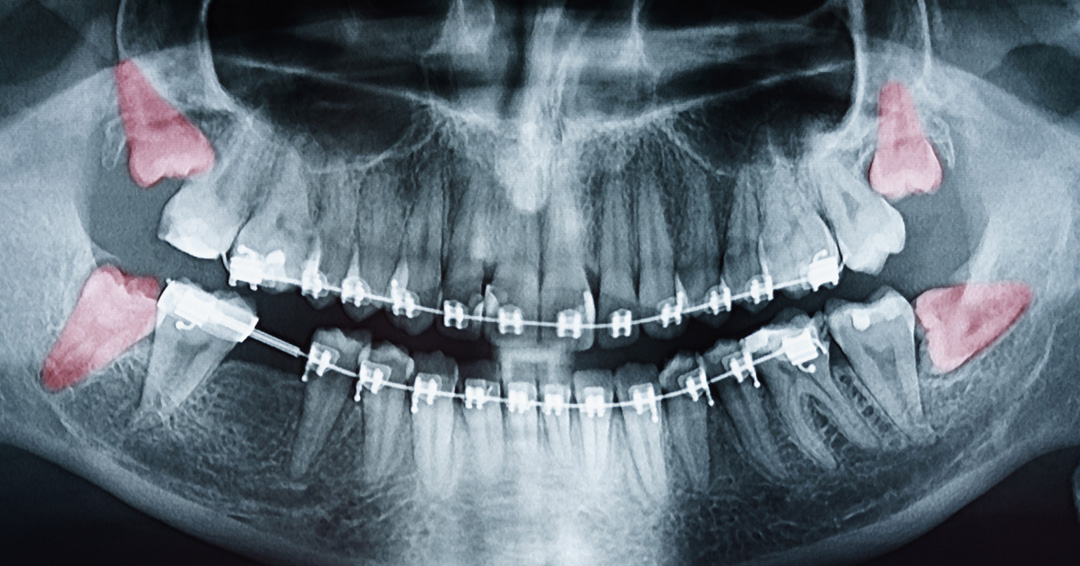

At Esteem Dental, we focus on creating a seamless, stress-free experience for teens and their families. The process starts with a detailed examination and digital X-rays to evaluate the position and condition of the wisdom teeth.